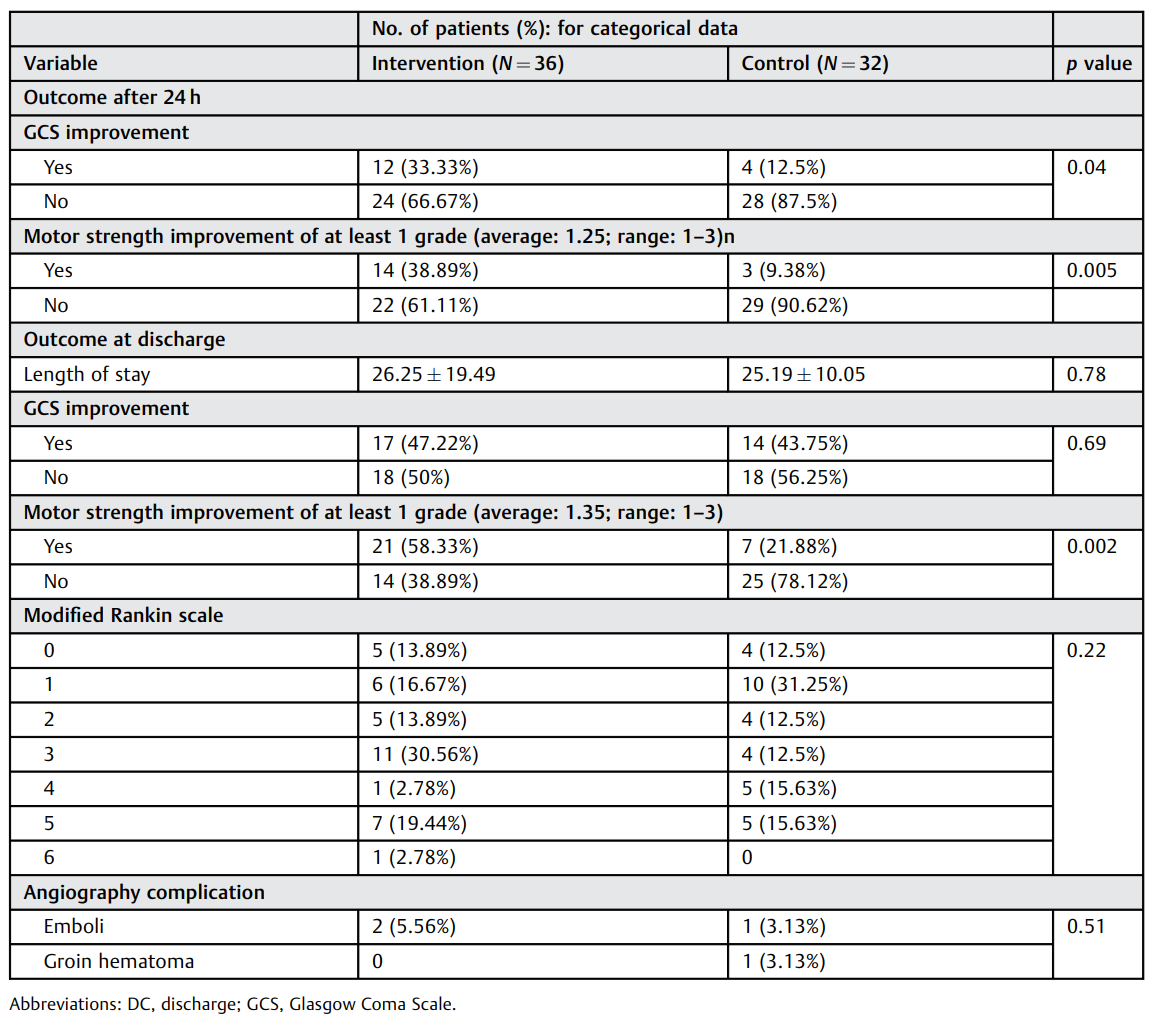

表1:住院期间患者临床结果。

aSAH后的CV对神经外科医生来说仍然是一个挑战。改善血流动力学、尼莫地平 (尤其是口服)和血管内治疗是标准治疗方案。在IANI与标准药物治疗的单中心随机对照研究中,IANI后患者肌力和GCS评分立即显著改善;出院时患者肌力进一步改善。但在长期随访中,两组的功能结局无显著差异。动脉灌注尼莫地平是近年来倍受关注的血管内治疗方法之一。在此之前,只有一项前瞻性研究(Hänggi等)在26例药物难治性CV患者中进行了尼莫地平动脉内给药。此研究结果显示动脉灌注尼莫地平可能对血管造影表现和临床结局有益,但只是暂时的。Park等人回顾性分析了73例CV患者,发现GCS评分的变化与血管直径的改善呈正相关,但对临床结局的影响尚不清楚。因此,他们认为IANI是合理的,但并不能总是预防迟发性脑梗死。此研究结果表明,出院时干预组中运动功能改善的患者显著较多。这一结果在随访期间未发现,可能是由于失访率较高(p=0.08)。此外,结果表明,IANI比自然恢复可更快地改善患者的意识。

IANI可有效治疗CV,无明显并发症。此研究是第一个显示24小时内和出院时肌力显著改善的随机对照试验。